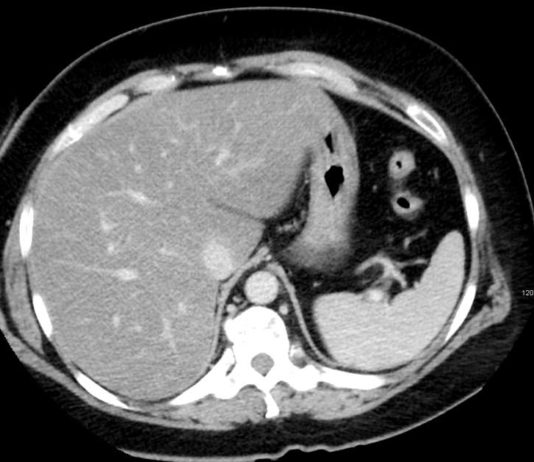

A gordura não é necessariamente prejudicial ao organismo humano, mas seu excesso pode causar diversas condições e enfermidades. Entre elas, está a esteatose hepática, popularmente chamada de "gordura no fígado". Entenda quais são os sinais de gordura no fígado e previna-se de quadros mais graves, como a cirrose.

O que é esteatose...